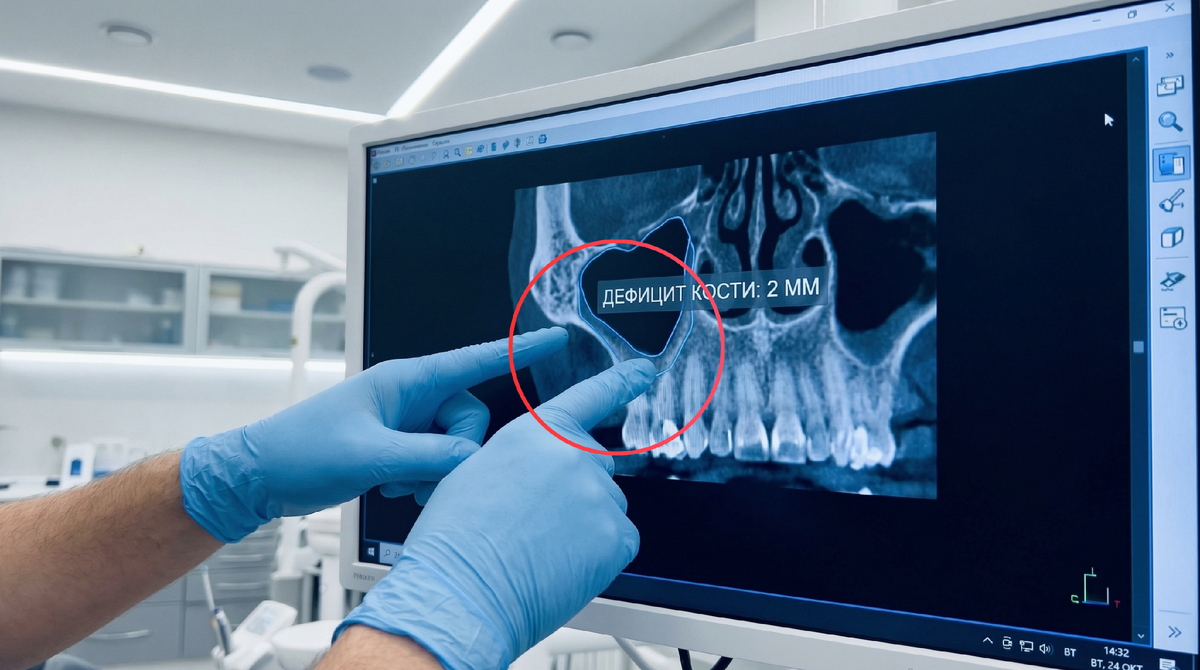

Я считаю, что главная беда современной стоматологии - это спешка. Меня бесит, когда пациенту обещают "всё за один день" там, где кости сохранилось едва 2 мм.

Теперь у нас есть не 2 мм, а целых 10 или 12 мм крепкой опоры. Хоть стейки жуйте, хоть яблоки грызите. На десятилетия.